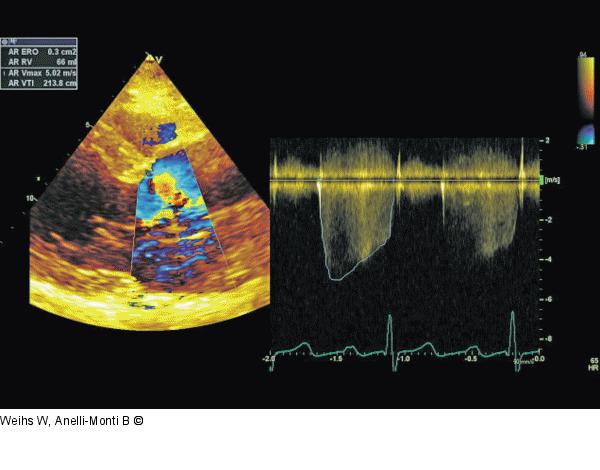

Abbildung 3: PISA-Methode Quantifizierung der Aorteninsuffizienz anhand der PISA-Methode. Sowohl der Radius als auch das CW-Signal werden von parasternal abgeleitet. Regurgitationsöffnung und -volumen sprechen für eine hochgradige Insuffizienz. |

Quantifizierung der Aorteninsuffizienz anhand der PISA-Methode. Sowohl der Radius als auch das CW-Signal werden von parasternal abgeleitet. Regurgitationsöffnung und -volumen sprechen für eine hochgradige Insuffizienz. |